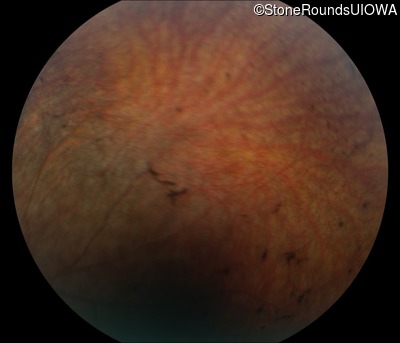

Fundus Photography - Right - No Light Perception

Exemplar

Fundus Photography - Left - No Light Perception